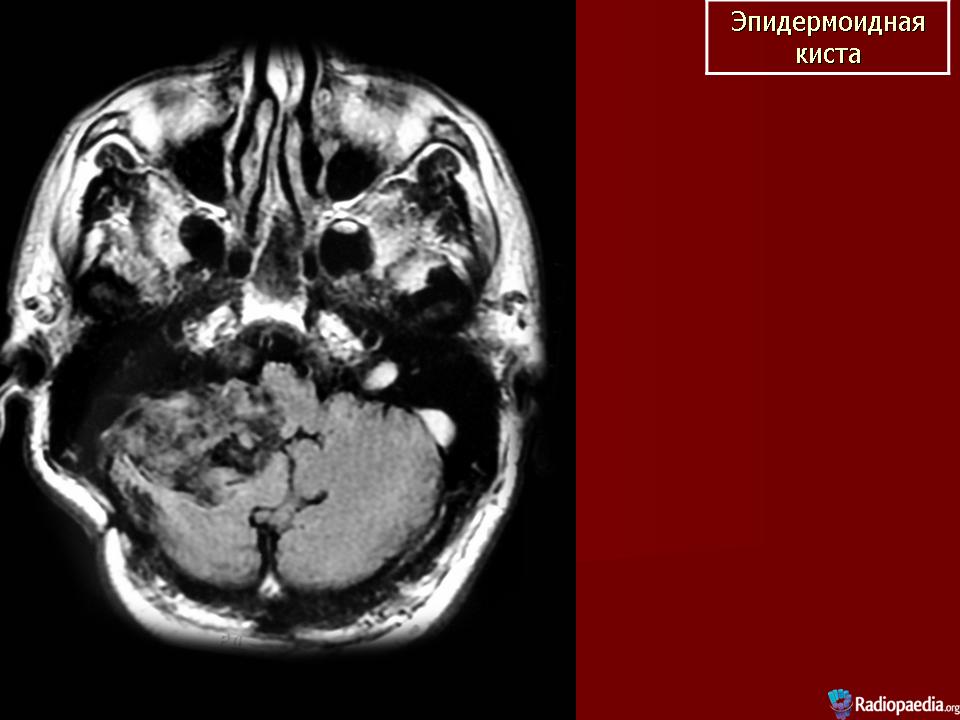

Эпидермоидная киста

Эпидермоидная киста.

ID: 5664 Epidermoid cyst (small pre-pontine) Dr Frank Gaillard - 5 Mar 2009 MRI demonstrates a small region in the pre-pontine cistern with distorti...

ID: 9772 Epidermoid cyst - cerebellopontine angle Dr Frank Gaillard - 23 May 2010 Characteristic appearance of an epidermoid cyst in the cerebellopon...

ID: 2609 Epidermoid cyst - cerebellopontine angle Dr Frank Gaillard - 7 May 2008 This patient had a right sided cerebellopontine angle mass (shown to be ...

ID: 4366 Epidermoid cyst - cerebellopontine angle Dr Frank Gaillard - 14 Aug 2008 Selected images from an MRI demonstrating both typical appearances and l...